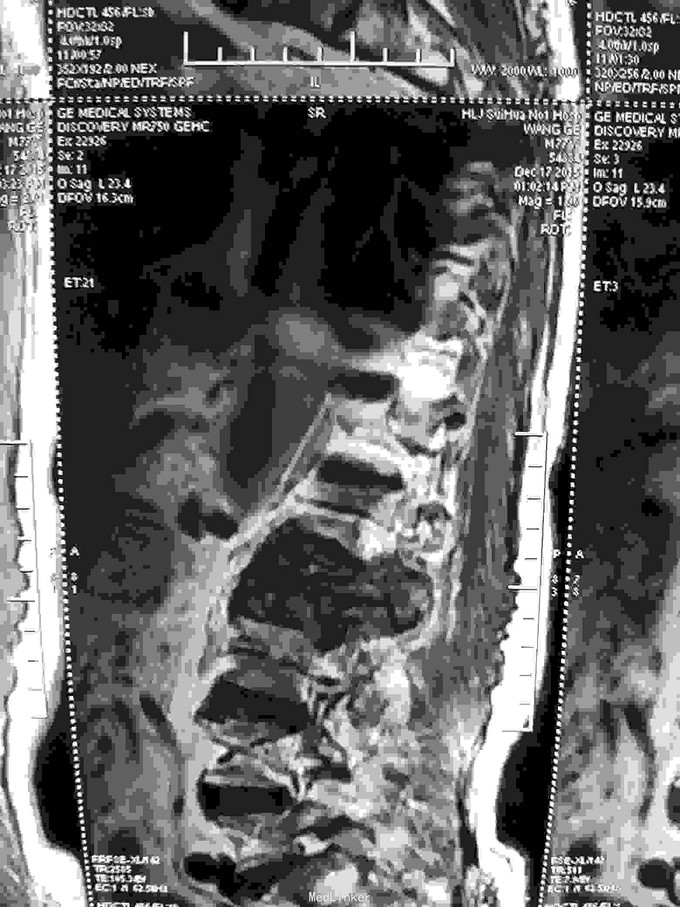

根据病史查体诊断:腰间盘突出症待确诊。应用消肿营养神经镇痛治疗。一天。查核磁共振示:腰椎多节段间盘突出伴椎管狭窄。第二腰椎骨破坏侵及椎板。部分突入椎管,脊髓受压。诊断:腰间盘突出伴椎管狭窄。第二腰椎转移癌,脊髓受压。经与家属沟通,查双肺CT:双肺下叶炎症。肺部纤维化。可见肿瘤阴影。肋骨及胸膜受累。胸椎部分骨破坏。最终诊断:双肺癌,胸椎,腰椎骨转移,脊髓受压。多节段腰椎间盘突出。病人至肿瘤科治疗。